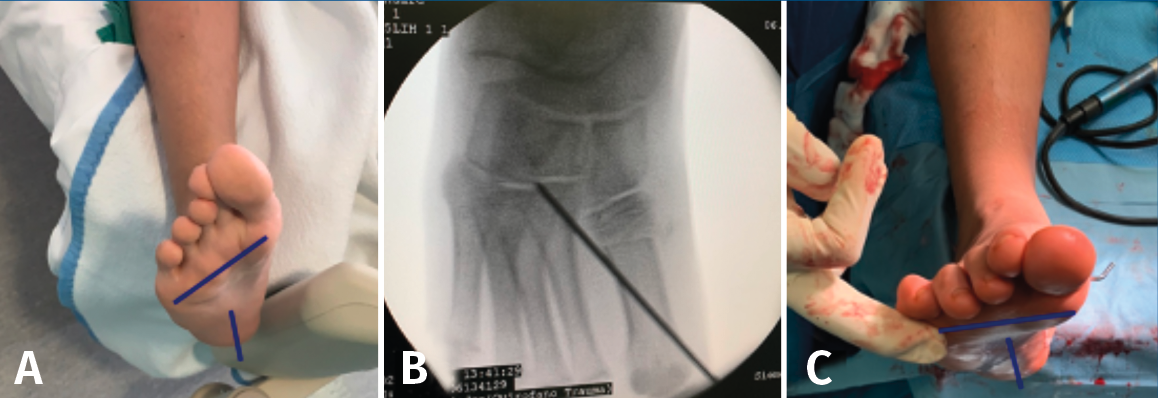

Técnica quirúrgica (Figura 12)

Figura 12. Osteotomía de alargamiento del calcáneo. A: osteotomía transversal de la tuberosidad anterior de calcáneo; con la ayuda del distractor, se hace la apertura, donde se rellena con injerto estructural; B: tendón peroneo (flecha), injerto óseo estructurado (◊), musculo pedio (•); C: control radiológico intraoperatorio (límite del injerto estructurado marcado con líneas discontinuas).

Se realiza una incisión longitudinal en la zona lateral del calcáneo, con precaución con el nervio sural y la rama cutánea del nervio fibular superficial y se separan los tendones peroneos hacia plantar. Se realiza una osteotomía transversal de apertura de la tuberosidad anterior del calcáneo a 1,5 cm de la articulación calcaneocuboidea y se rellena con auto- o aloinjerto estructural de 8-10 mm. Una aguja de Kirschner (AK) calcaneocuboidea evita la subluxación del cuboides y ayuda a estabilizar el injerto.

En ciertos casos, es necesario alargar el tendón peroneo lateral corto, que es valguizante y queda muy tenso tras la intervención. El peroneo lateral largo se debe conservar por ser cavizante (pronador del antepié).

Esta técnica genera frecuentemente una supinación residual del antepié que puede necesitar corrección mediante osteotomía de pronación.